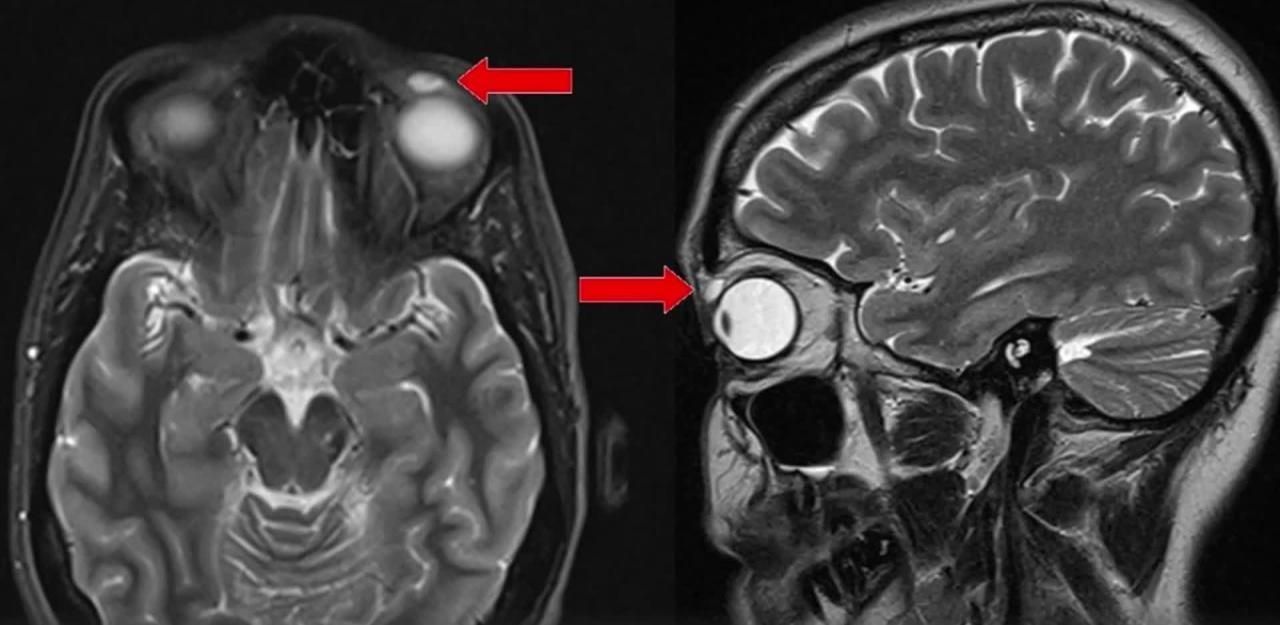

Ärzte finden Kontaktlinse nach 28 Jahren im Auge

Frau musste nach Urlaub Auge entfernt werden